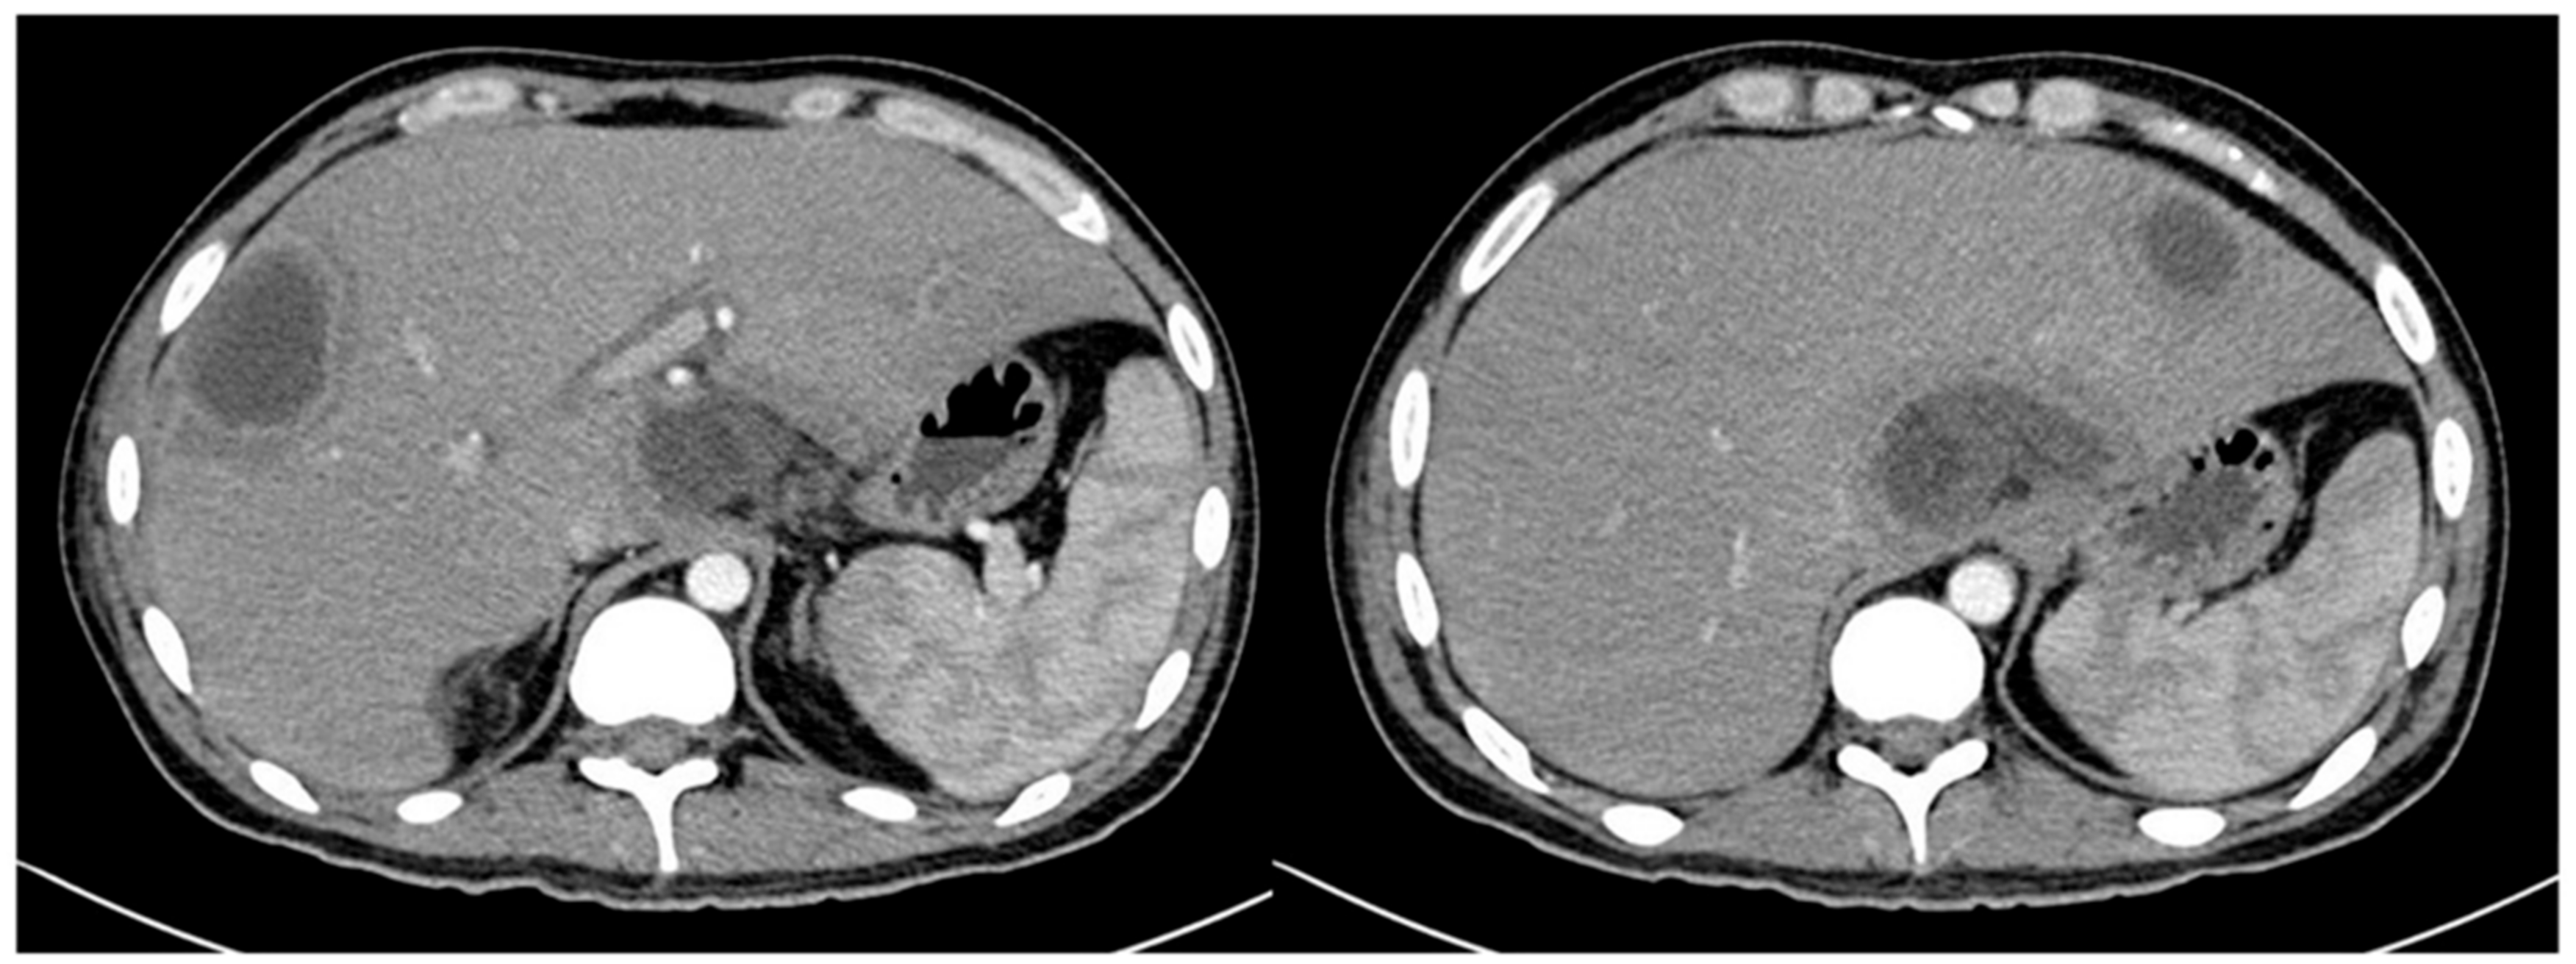

Two days later, he had come back with an acute abdomen, although afebrile. Vital constants at admission were: BP: 107/78 mmHg, HR: 90 bpm, RR: 20 rpm, T °: 36.5 °C, weight: 55 Kg, height: 1.62 m, BMI: 21 Kg/m2. His blood tests showed leukocytes of 0.32 × 103/μL, absolute neutrophils 0.0032 x103/μL, hemoglobin 5.7 g/dL, platelets 35 × 103/μL, creatinine 0.66 mg/dL, ALT 174 IU/L, AST 82 IU/L, ALP 1004 IU/L, GGT 572 IU/L, total bilirubin 8 mg/dL, conjugated bilirubin 6.4 mg/dL, unconjugated bilirubin 1.62 mg/dL, LDH 287 IU/L, albumin 1.7 mg/dL, C reactive protein 8.4 mg/dL. The patient underwent exploratory laparotomy which revealed sigmoid perforation. Sigmoidectomy and colostomy were performed. The initial pathology report was diverticulum perforation. Forty-eight hours later, he presented moderate diffuse abdominal pain, and temperature > 38 °C. The blood cultures were negative. Administration of Meropenem, caspofungin and Filgastrim was empirically initiated. Contrast abdominal tomography (CT) showed diffuse liver lesions consistent with liver abscesses (Figure 1).

Figure 1.

Abdominal CT scan with intravenous contrast, which shows: Diffuse and poorly defined hypodense lesions, one located in the liver segment II measuring 3.4 cm, another located in the caudate lobe measuring 7 cm, and another located in the hepatic segment VII with extension to segment VI measuring 7 cm; consistent with liver abscesses.